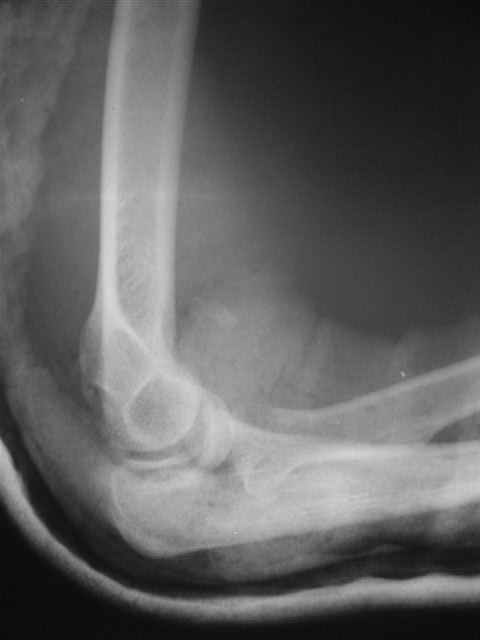

Вывих костей предплечья и перелом головки лучевой кости. |

Уважаемые коллеги!Помогите с источниками литературы по вопросу о сроках резекции головки лучевой кости и гетеротопической оссификации после вывиха костей предплечья. Необходимо ответить на жалобу, где больная просит возместитьматериальные затраты на лечения с лечащих врачей, которые участвовали влечении с 4.09.04 по 10.11.04, объясняет, что врачи нарушили стандарты леченияи поздно направили на оперативное лечение.История болезни, женщина 46 лет упала дома 4.09.04, получила заднелатеральныйвывих костей предплечья и перелом головки лучевой кости, под местной анестезиейвывих вправлен, на контрольной рентгенограмме соотношение отломков головкилучевой кости расценено, как удовлетворительное. Наложена задняя гипсовая шина.Лечение: холод, кетанов 3 дня, магнитотерапия, ЛФК пальцев, рентген контрольчерез 7 дней, с 8.09.05 наклофен 50 мг 2 раза в день. 11.09.04 на контрольной рентгенограмме состояние отломков прежнее. 30.09.04. Гипсовая шина снята через 26 дней. Лечение: ЛФК, массаж, электрофорезлидазой.9.10.04. В левом локтевом суставе сгибание 80, разгибание 120.19.10.04. Сгибание 80, разгибание 140, ротационные движения в пределах 10 гр.28.10.04. Сгибание 80, разгибание 150, ротационные движения в пределах 10 гр.10.11.04. На рентгенограмме локтевого сустава отмечается гетеротопическаяоссификация.Учитывая неэффективность консервативного лечения, больная направлена на оперативноелечение.Больная по собственным каналам уехала в г. Киев, где произведенарезекция головки лучевой кости, после операции развился неврит лучевого нерва.На данный момент больная продолжает лечение у нейрохирурга.-- С уважением,Анатолий Борзунов

В локтевом суставе сгибание 80*, разгибание 150*, наружняя ротация 25*, внутрення ротация 35*.

До операции 10* амплидуда в обе стороны.